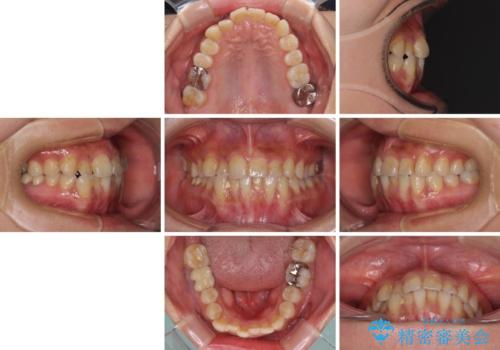

- 上下のクロスバイトと前歯のデコボコを気にして来院された患者様です。

骨格的に下顎がやや前方にあり、奥歯にクラウンが装着されているため、矯正治療後半の不安定な咬み合わせを避けるのであればワイヤー矯正がおすすめとなりますが、希望によりインビザラインにて治療を行うこととしました。

インビザラインを用い、IPR(歯と歯の間を削る)と歯列全体を拡大させることで、歯並びを整えていくこととしました。

懸念されたとおり、右下のクラウン部分が全く咬み合わず、仕上げの段階で治療期間が長くなりました。